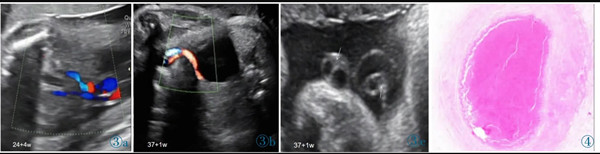

圖3 誤診為單臍動脈病例的超聲圖像。圖3a:孕24+4 周,膀胱兩側(cè)均可見UA 血流信號;圖3b:孕37+1 周,膀胱一側(cè)UA 血流信號消失;圖3c:臍帶橫切面見臍靜脈呈“C 形”包繞2 條UA,箭頭所示其中1 條UA 管腔細(xì)小,內(nèi)為稍高回聲(血栓)填充。圖4 臍帶病理(HE 染色)。UA 內(nèi)見血栓形成,管壁彈力纖維梗死。Figure 3.Ultrasonography misdiagnosed as single umbilical artery.Figure 3a: At 24+4 weeks,the blood flow of two UAs is seen in both sides of bladder.Figure 3b: At 37+1 weeks,only one UA is seen in the level of bladder.Figure 3c: In the cross section of umbilical cord,two UAs are surrounded by umbilical vein.As indicated by the arrows,one UA has smaller lumen which is filled with a slightly higher echo(thrombi).Figure 4.The pathological finding of umbilical cord (HE stain).The UA lumen is filled with thrombi.The necrosis of elastic fibers are found in arterial wall.

2.4 產(chǎn)時情況及產(chǎn)后病理資料

產(chǎn)時肉眼可見11 例臍帶長度均正常,其中4 例(36.4%)臍帶高度螺旋,1 例(9.1%)帆狀胎盤。7 例產(chǎn)時病歷描述可見1 條UA 外觀全程/部分呈暗紅色,1 例UA 部分呈土黃色,橫斷面均可見血栓形成。3 例病歷資料中未描述臍帶外觀。病理結(jié)果提示11 例臍帶橫斷面均提示有2 條UA,鏡下所見其中1 條UA 內(nèi)血栓形成(圖4)。